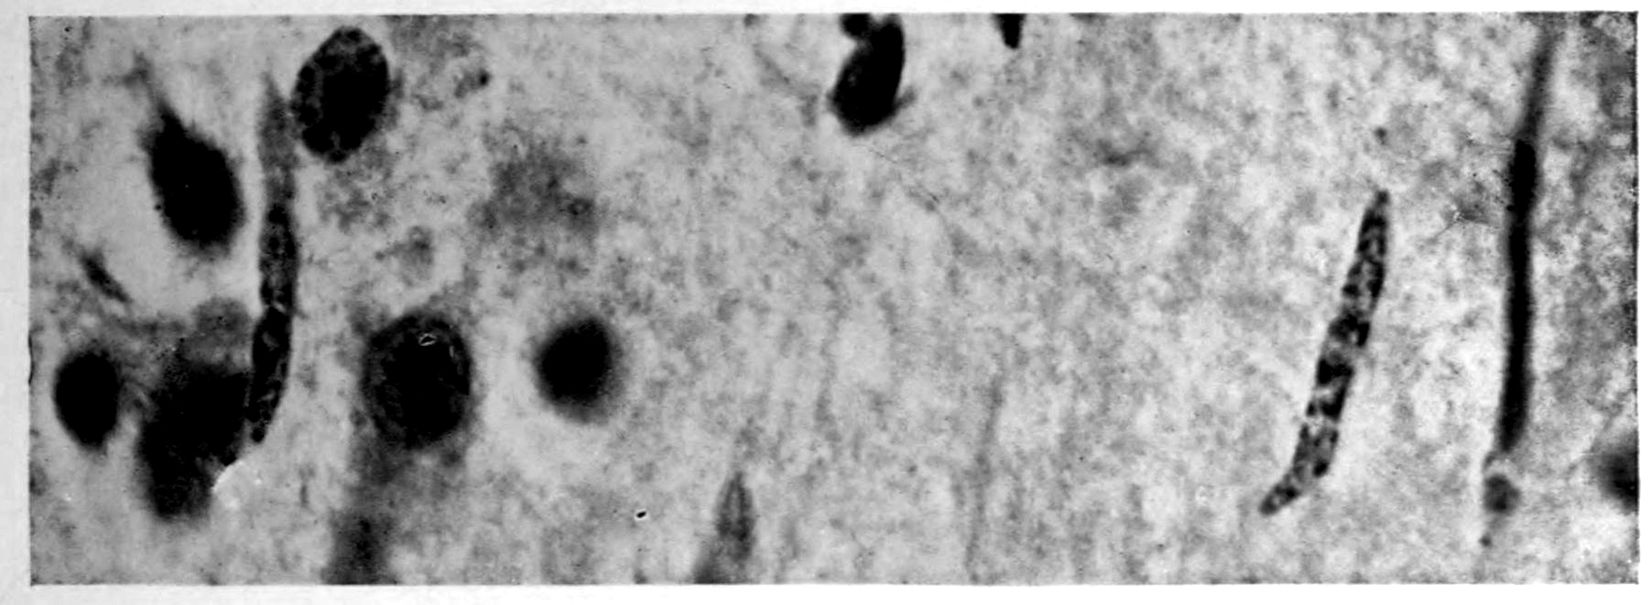

A. Normal postcentral cortex. (Compare B.)

B. Nerve cell losses. Perivascular deposits of mononuclear cells, amongst which are numerous plasma cells. Note decrease in number of nerve cells. Note irregular disposition of nerve cells. From paretic neurosyphilis.

Apparent new formation of small blood vessel. Photographed by Dr. A. M. Barrett.

Rod cells (Stäbchenzellen) in paretic neurosyphilis. Photographed by Dr. A. M. Barrett.

Granular ependymitis—microscopic appearance of a marked example of “sanding” of ventricle.